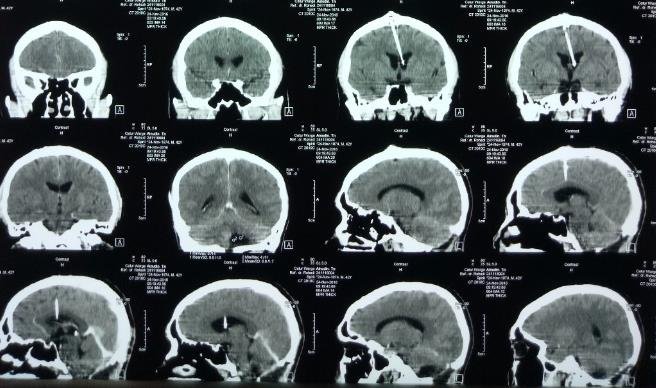

Ecco alcuni esempi del loro utilizzo. I raggi X viaggiano attraverso il corpo e sono assorbiti in modo diverso dai diversi tessuti: l'immagine che producono è fatta di zone più o meno intense (chiaro/scuri) a seconda della quantità di radiazione assorbita da quel dato organo; la Tomografia Assiale Computerizzata (o TAC) crea immagini corrispondenti a sezioni trasversali del corpo (come se analizzasse il corpo per fettine sottili); la radioterapia è usata nei trattamenti anticancro, mentre in medicina nucleare sostanze radioattive vengono iniettate nell'organismo per scopi terapeutici, diagnostici o per ricerca.

Here are some examples. X-rays travel through the body and are absorbed differently by the different tissues, giving an image that is more or less intense according to the different amounts of radiation absorbed by a given tissue; computerized axial tomography scans (in short CT/CAT scans) create cross-sectional images of the body; in anticancer treatments (radiotherapy) and in nuclear medicine, radioactive substances are administered to a patient for therapeutic, diagnostics or biomedical research purposes.